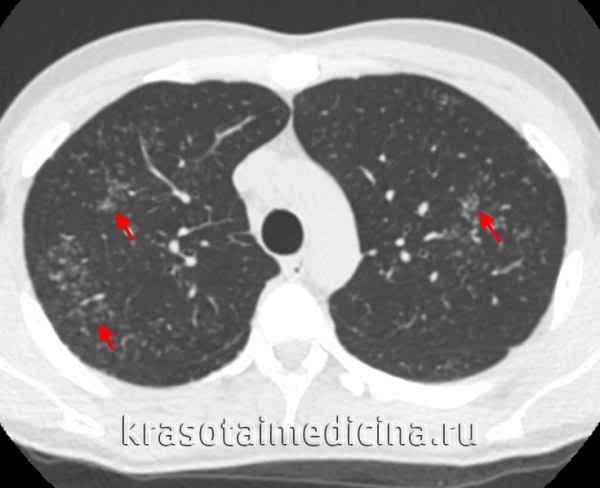

Характерные изменения при саркоидозе выявляются при рентгенографии легких, в ходе КТ или МРТ легких - определяется опухолевидное увеличение лимфоузлов, преимущественно в корне, симптом «кулис» (наложение теней лимфоузлов друг на друга); очаговая диссеминация; фиброз, эмфизема, цирроз легочной ткани. У более половины пациентов с саркаидозом определяется положительная реакция Квейма – появление багрово-красного узелка после внутрикожного введения 0,1—0,2 мл специфического саркоидного антигена (субстрата саркоидной ткани больного).

КТ органов грудной клетки. Множественные типичные саркоидозные очаги субмиллиметрового диапазона с диффузным распространением